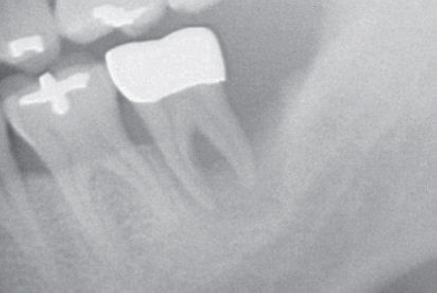

Pre-Op view

Post-Op